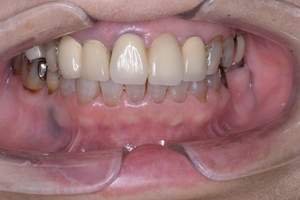

治療前 1

治療後 1

治療前 2

治療後 2

治療前 3

治療後 3

| 年齢 | 58歳・女性 |

|---|---|

| 主訴 | 前歯の着色除去希望 |

| 治療内容 | エアフロー |

| 費用 | 合計:5,500円 (2024年8月現在) |

| 治療期間 | 60分 |

| リスク・副作用 | 呼吸器疾患のある方や放射線治療を行っている方、ナトリウム摂取制限を必要とする方や妊娠中の方は処置を受けられないことがあります。 施術を受ける際、舌や歯肉に当たった粒子でチクチクとした痛みを感じることがあります。 |

| 治療方針 | 歯周病と虫歯の治療を担当医と相談し進めていく予定です。 |

| 担当者所見 | 約4年ぶりの来院でした。他の歯医者に行っても満足いくクリーニングをしてもらえず悩んでいる様子でした。問診時には手で口元を隠すようにお話されていましたが、エアフロー後は笑顔でお話するようになっていました。 |